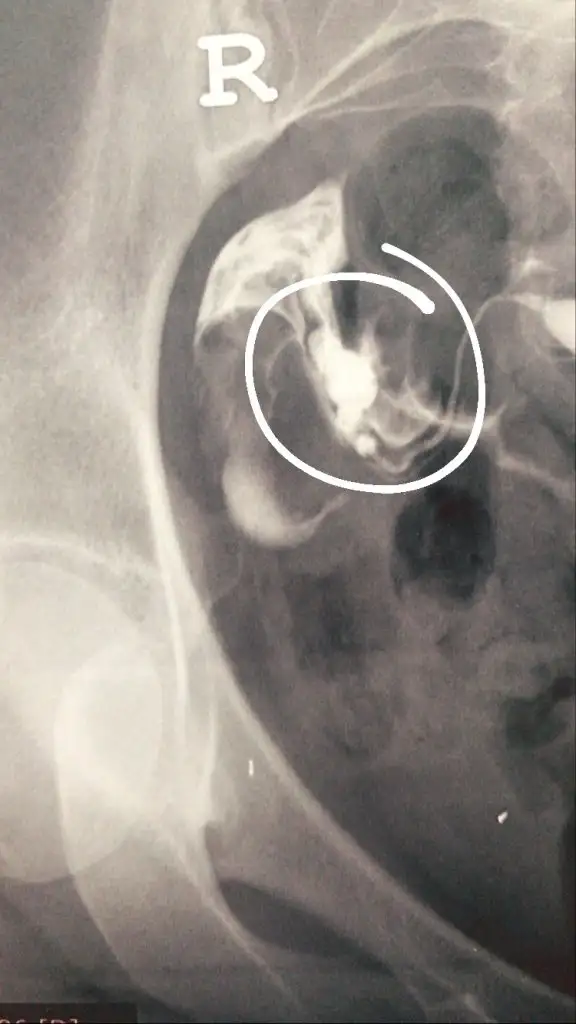

Yumurta değil bence canım. Adet sonrası hemen yumurta olmaz ki. Bu arada canın acıdı mı nasıl çektirdin hsg. Bende Cumartesi gidicem çektirmeye çok korkuyorumKızlar dün hsg çektirdim bu küçük şeyler yumurta olabilir mi

Hsg yumurta görülmüyor diye biliyorum amaKızlar dün hsg çektirdim bu küçük şeyler yumurta olabilir mi

Direk yumurta değil ama yumurtalık onlar çift taraflı. O Yumurtaligin içinde yumurtalar var. Yumurtalarında azalma varsa hsg de boyutları daha küçük görünüyor. Senin gayet iyi büyük yumurtalik.Kızlar dün hsg çektirdim bu küçük şeyler yumurta olabilir mi